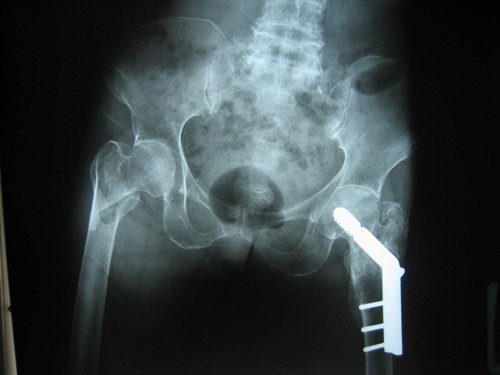

แนวทางการรักษากระดูกสะโพกหักในปัจจุบันที่ดีและเหมาะสมที่สุด คือ การรักษาด้วยการผ่าตัด จากงานวิจัยของคณะแพทยศาสตร์ มหาวิทยาลัยเชียงใหม่ และโรงพยาบาลมหาราชนครราชสีมาพบว่า การรักษาผู้ป่วยด้วยวิธีการไม่ผ่าตัด นอนดึงให้กระดูกติด จะทำให้ผู้ป่วยมีโอกาสเสียชีวิตมากกว่าผู้ป่วยในกลุ่มที่รักษาด้วยการผ่าตัดมากถึง 2 – 3 เท่า ดังนั้น การรักษาผู้ป่วยกระดูกสะโพกหักอันเนื่องมาจากโรคกระดูกพรุนด้วยการผ่าตัดจะช่วยรักษาให้ผู้ป่วยสามารถลุกเดิน เคลื่อนไหวได้ไวขึ้น มีการเกิดโรคแทรกซ้อนน้อย และช่วยลดอัตราการเสียชีวิตลงได้ การผ่าตัดส่วนใหญ่นั้นขึ้นอยู่กับตำแหน่งการหักของกระดูกสะโพก บางครั้งก็ใช้วิธีการผ่าตัดยึดตรึงกระดูกด้วยแผ่นเหล็ก บางครั้งก็ผ่าตัดเปลี่ยนข้อสะโพกเทียม